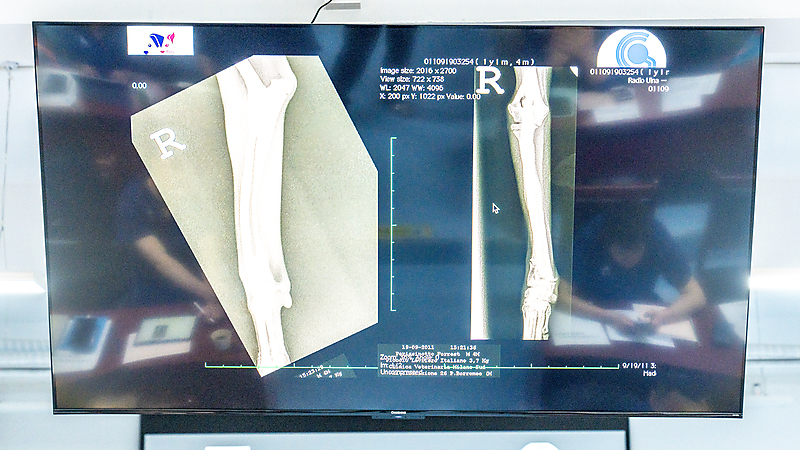

BlueSAO佰陆畸形矫正大师班第二天的精彩课程,正在火热进行中~Dr.Massimo带着饱满热情登台,聚焦前肢肱骨与桡骨畸形病例诊断,用丰富的临床实例为现场医生们拆解核心知识点。课程中,他分享了多个不同类型的畸形病例,引导现场医生共同探讨诊疗思路、交流临床经验,在传递高质量专业内容的同时,也充分调动了大家的参与感,切实保障每一位学员的课程体验,让每一分钟的学习都更具价值!

第二节课,Massimo 老师带来桡骨畸形矫正专题内容。课程针对前肢不同位置的畸形问题,给出精准适配的矫正思路与方案。Dr. Massimo 结合海量一线临床病例,将复杂知识点梳理得清晰易懂,讲解细致深入。